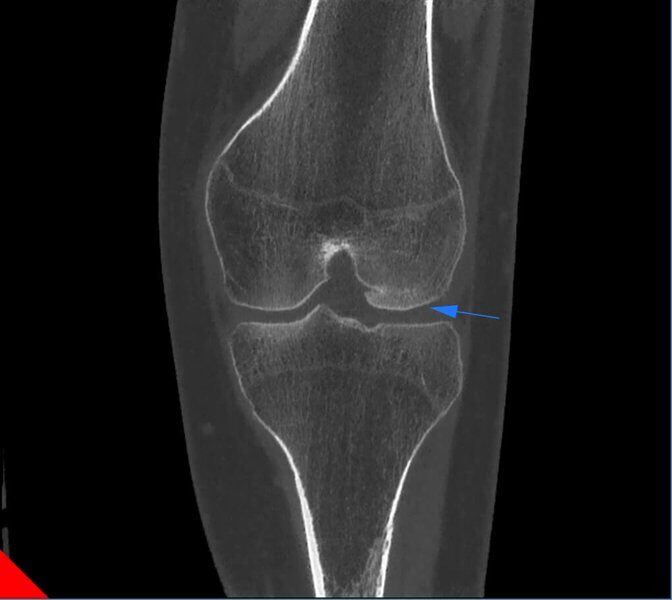

Frattura del Condilo Femorale laterale